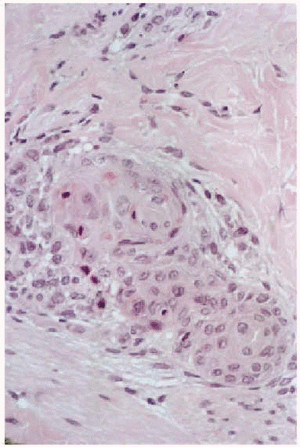

Cinco días después del final de la radioterapia la niña es hospitalizada por neutropenia febril con foco respiratorio, iniciándose tratamiento con cefepime y codeína. Al día siguiente se observó la aparición de unas placas eritematovioláceas, conformadas por micropápulas no foliculares, distribuidas en la región lumbar y en la zona del abdomen, con predilección por los bordes de la cicatriz de laparotomía (figs. 1 y 2). En el estudio histopatológico se evidenció una metaplasia escamosa madura de las porciones rectas de los conductos de las glándulas ecrinas sin afectación de los ovillos (fig. 3). Se observaban asimismo frecuentes células necróticas, queratinización de las luces y aislados queratogranulomas que entraban en contacto con la luz glandular (figs. 4 y 5). El diagnóstico histológico fue de siringometaplasia escamosa ecrina. La enferma continuó tratamiento quimioterápico, a pesar de lo cual las lesiones evolucionaron espontáneamente hacia la curación en un período aproximado de 1 mes, quedando una hiperpigmentación residual que se fue borrando paulatinamente.

Fig. 4.--Glándulas ecrinas con metaplasia escamosa e infiltrado inflamatorio periférico.

Fig. 5.--Aproximación. Transformación de las células ductales en células escamosas. Aisladas células necróticas. Queratogranuloma.